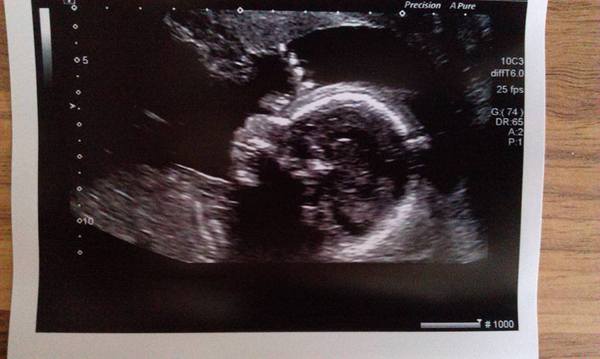

Realised I never posted my 20 week scan pic, here's the little fella!

Jan 2016 #8 Enjoying second trimester and 20 week scans